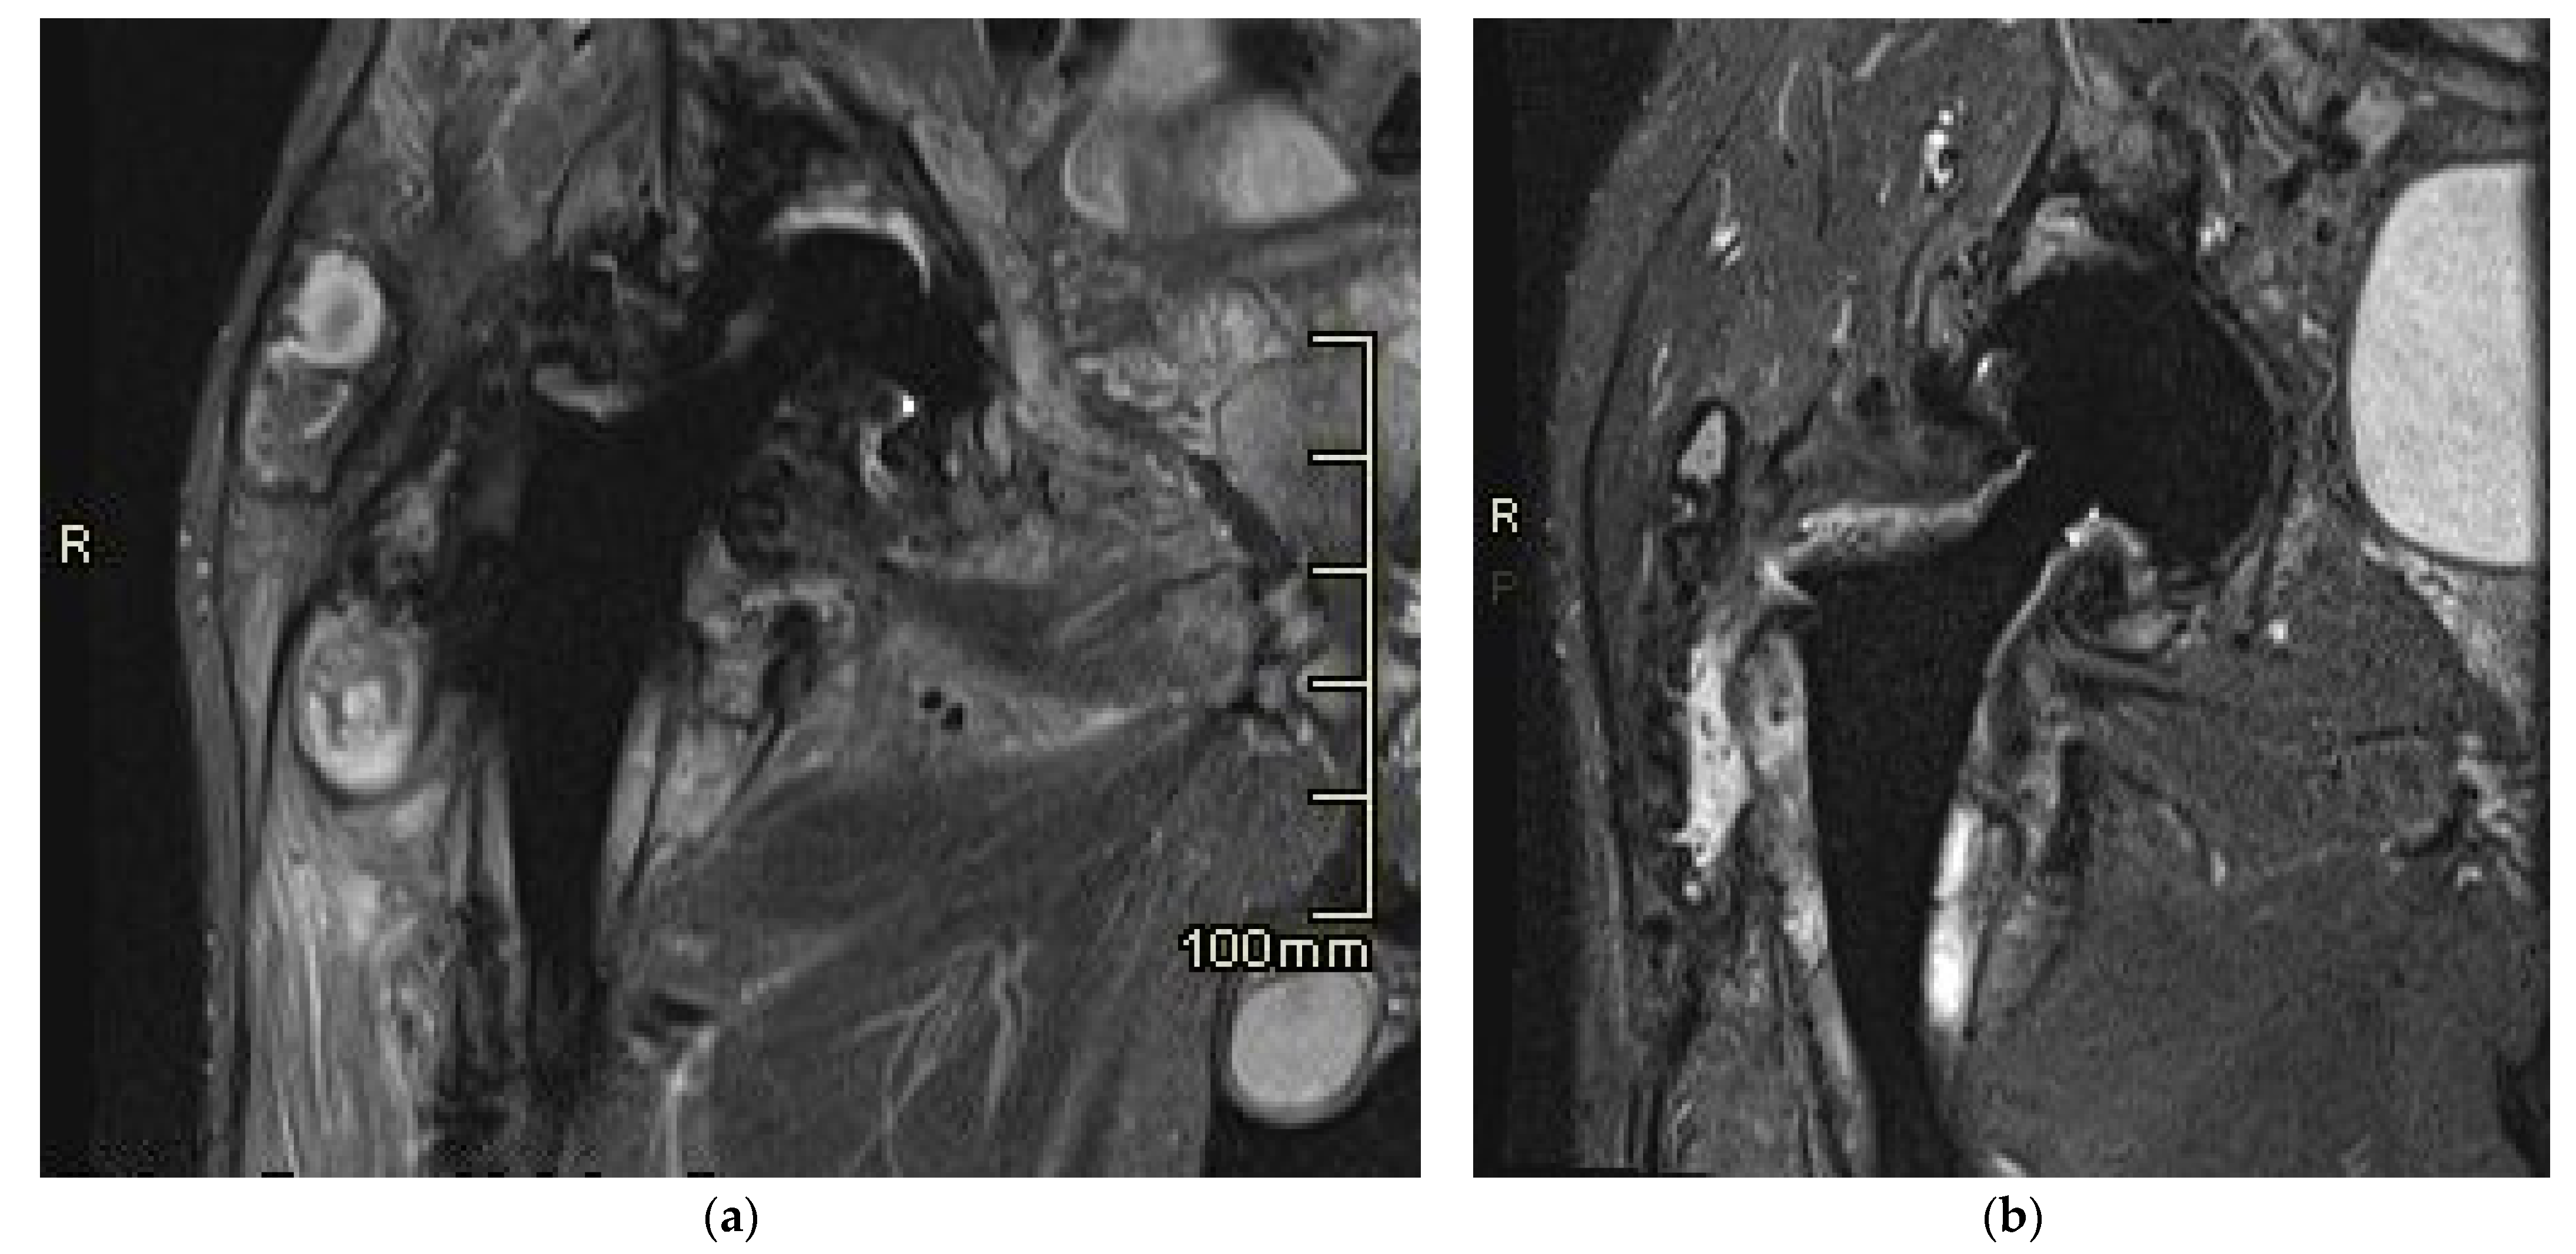

2.3. MR Imaging